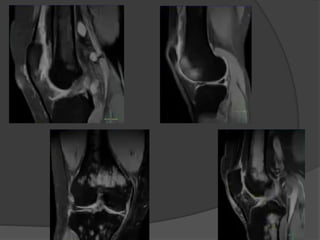

Condromalacia

 El grado se determina por artroscopía.

 Grado 0: Normal.

 Grado 1: Reblandecimiento del cartílago.

 Grado 2: Ulceración poco profunda, menor del 50% del espesor.

 Grado 3: Ulcera profunda, mayor del 50% del espesor, pero que

no se extiende al hueso.

 Grado 4: Ulcera con exposición del hueso subcondral.

Grado 0

Grado 1

Grado 2

Grado 3

Grado 4